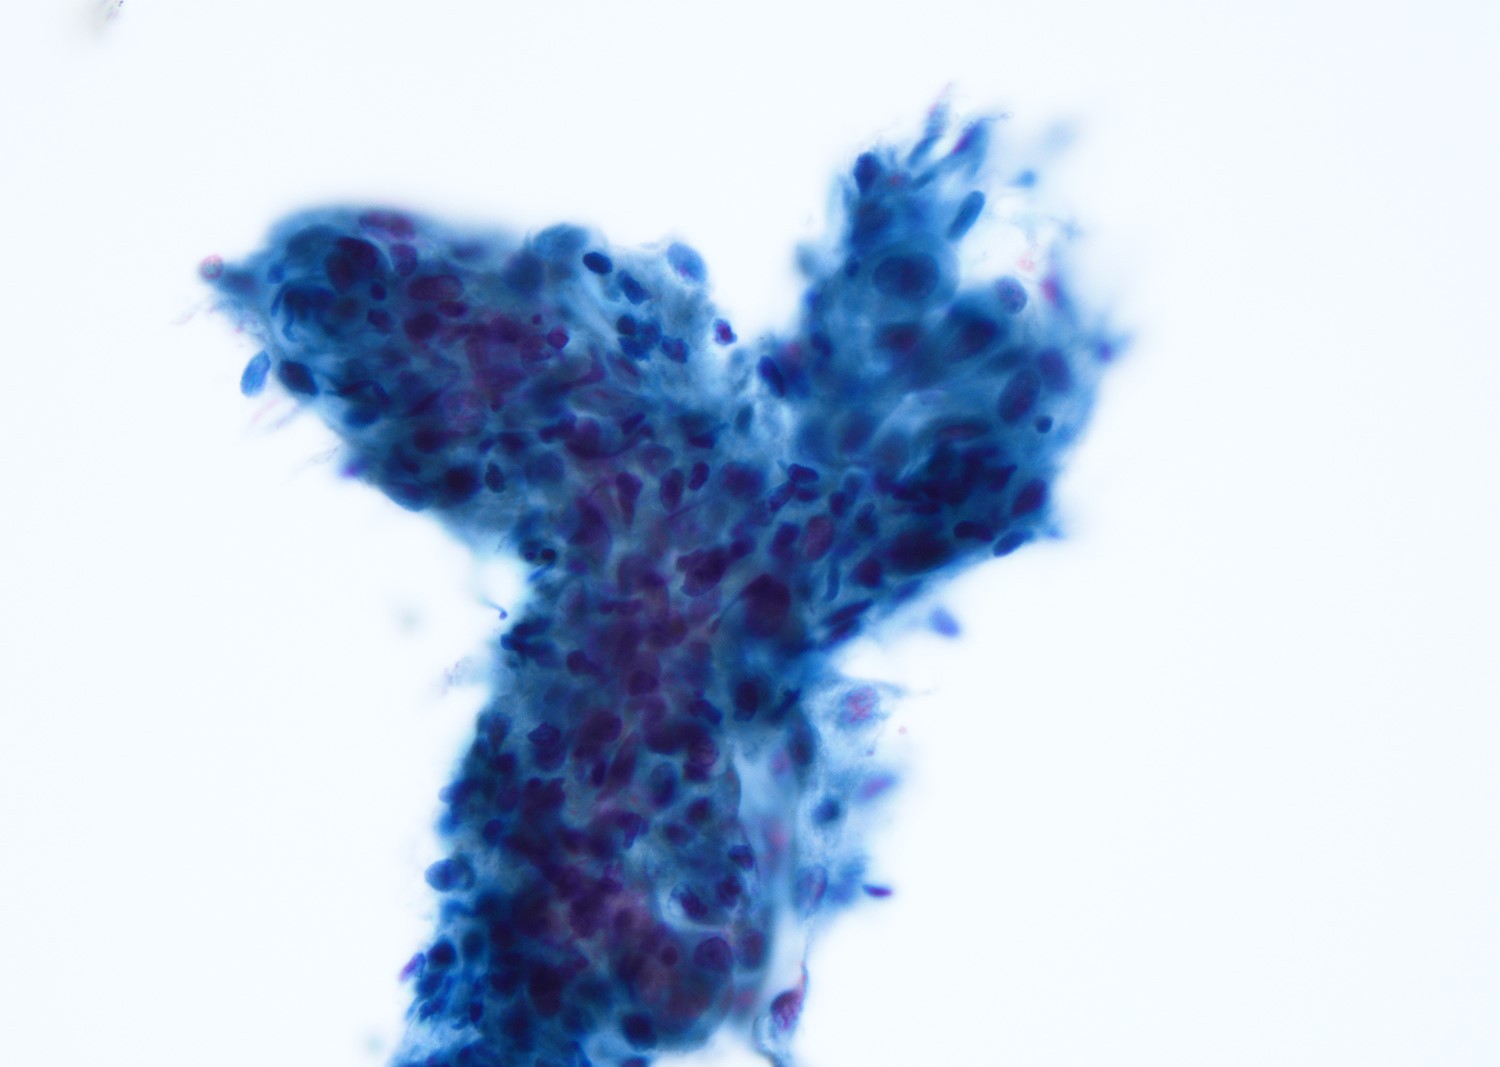

Cytology description

- Mature nucleated squamous cells with variable reactive atypia, anuclear cells and squamous epithelium (Int J Surg Case Rep 2017;41:383, Diagn Cytopathol 2012;40:684)

- Polymorphous lymphocytes and aggregates of epithelioid histiocytes

- Proteinaceous background

- Variable presence of acute inflammation, and bland appearing mucinous ductal cells and ciliated columnar cells

- Scant cellularity, abundant proteinaceous background, lack of squamous cells and epithelial cells, marked atypia of epithelial cells, abundance of lymphocytes pose diagnostic challenges

Cytology images